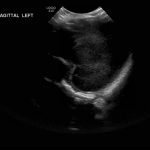

Age: 4 days (born at 24 weeks)

Sex: Male

Indication: Evaluate for germinal matrix hemorrhage

Grade 2 germinal matrix hemorrhage

Sample ReportLeft germinal matrix hemorrhage involving the caudothalamic groove and layering in the occipital horn of the left lateral ventricle without hydrocephalus (grade 2).

No abnormal brain parenchymal echogenicity or extra-axial collections.

Premature sulcation pattern.